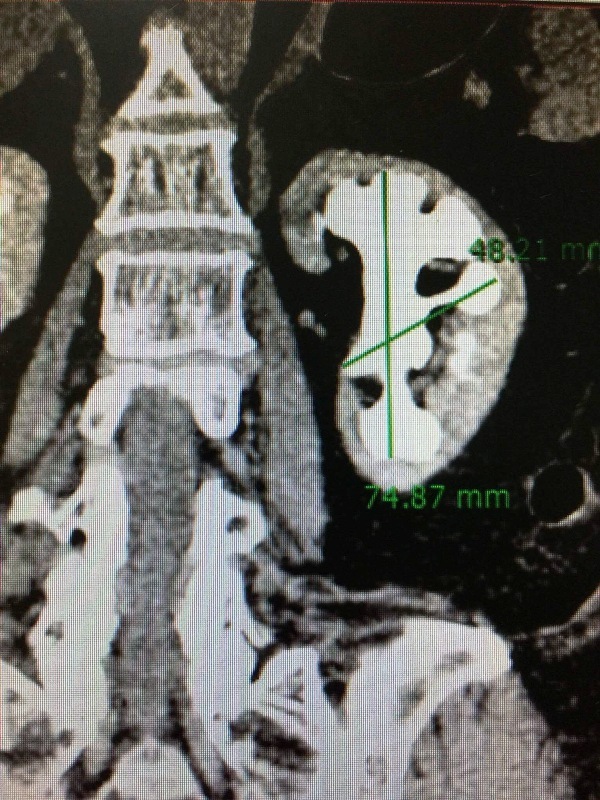

Qua chụp CT – scan, các BS phát hiện người bệnh bị sỏi san hô kích thước 74 mm x 48 mm, chiếm hết toàn bộ thận và các đài thận.

| Sỏi thận lấp đầy các đài thận của bệnh nhân, nhìn như một tảng san hô dưới biển |

Viên sỏi lấp đầy toàn bộ các nhánh đài thận, nhìn như một tảng san hô dưới biển. Đây là 1 trường hợp sỏi thận phức tạp, hiếm gặp - BS Nguyễn Hoàng Đức, Trưởng khoa Tiết niệu cho hay.